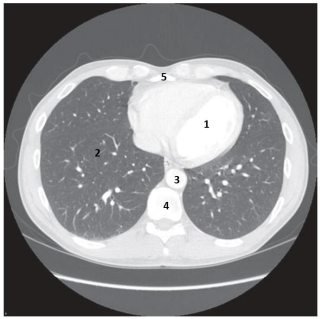

Observe a imagem a seguir.

Assinale a opção que identifica corretamente o número indicado na imagem